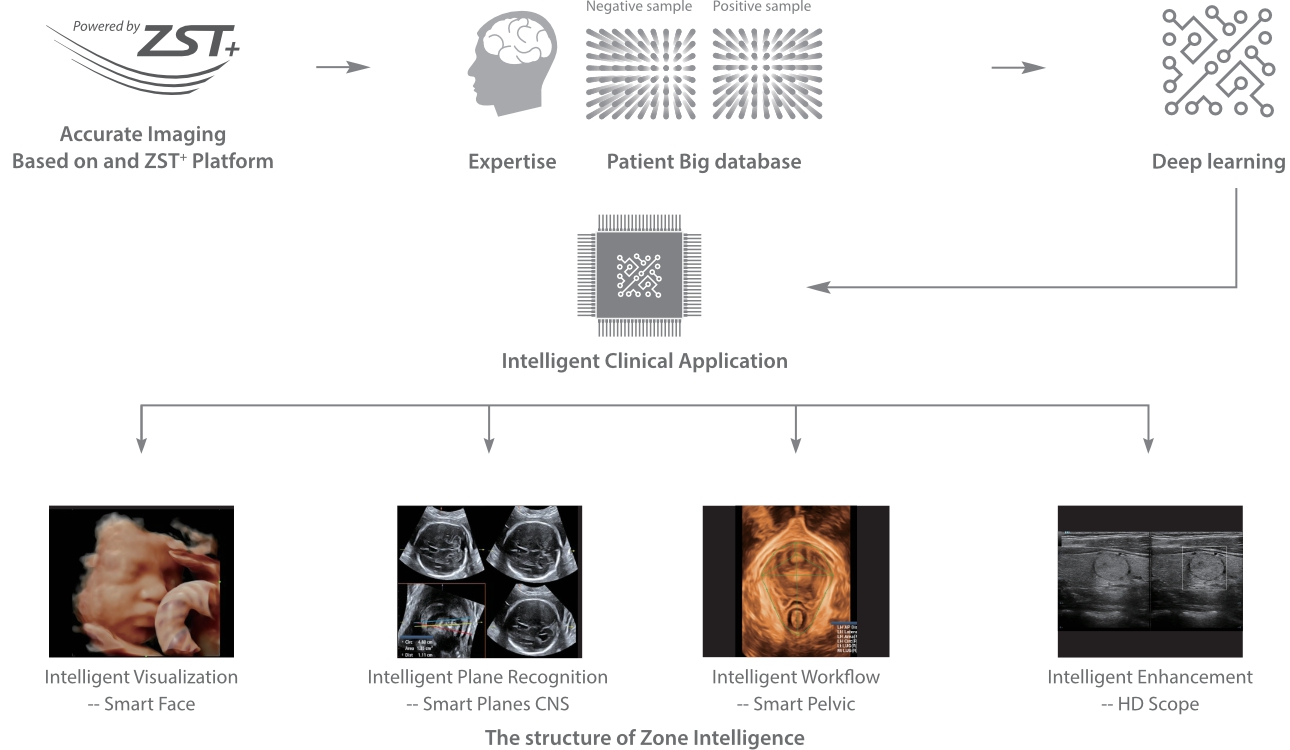

con Zone?Intelligence

Desde que se fundó la compa?ía, Mindray ha explorado incansablemente nuevas formas de mejorar la confiabilidad del diagnóstico. Con la revolucionaria tecnología de ZONE Sonography?, la nueva plataforma ZST+ de Resona?7 lleva la calidad de la imagen por ecografía a un nivel superior mediante el procesamiento de datos de canal y la adquisición de zona.

Además de la calidad de imagen de primer nivel, Resona?7 también mejora las capacidades de investigación clínica con el revolucionario V?Flow para la evaluación hemodinámica vascular y con la adquisición de planos más inteligente a partir de conjuntos de datos 3D para el diagnóstico del SNC fetal. Al combinar el funcionamiento multitáctil basado en gestos más intuitivo y todas las características clínicas esenciales, Resona?7 realmente lidera las novedades en innovación de ecografías.